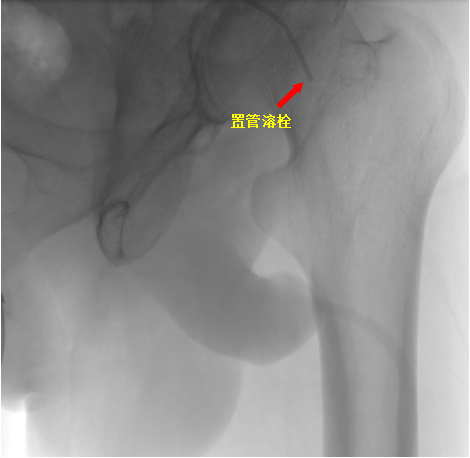

手术当天,易主任在病人左下肢动脉多处进行造影,考虑为血栓造成动脉闭塞,导管退至左侧髂外动脉起始部行溶栓治疗。

患者若伴血栓形成或血栓栓塞,通常可经导管注射尿激酶先行溶栓;部分患者可配合试行血栓抽吸术,以改善疗效。此方法也适用于介入治疗后的急性血栓形成(可经导管注入尿激酶溶栓,必要时留置导管2天~3天,进行持续溶栓,溶栓后再次进行动脉造影,评估溶栓效果,必要时行血管成形术等进一步治疗)。